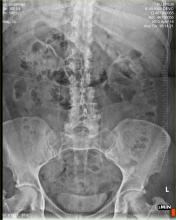

May 4, 2022 — Understanding the most recent mechanisms of ballistic trauma and injury patterns aids to guide radiologists’ interpretation, an award-winning Electronic Exhibit noted this morning during the 2022 ARRS Annual Meeting in New Orleans, LA.

Both direct and indirect injury is caused by the bullet and the shockwave created around its path.